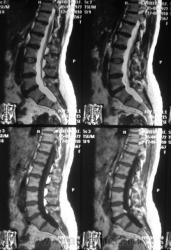

Болезнь Легг - Кальве - Пертеса?

В течение года боли в тазобедренном сустава и поясничном отделе позвоночника.

Позвоночник.